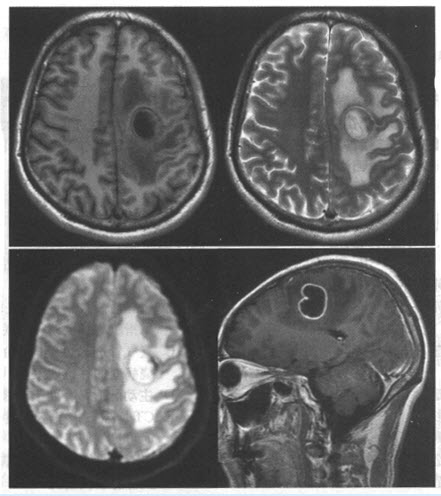

患者,男,47岁。低热、头痛半个月余,MRI检查如图。

该患者符合哪种疾病()

A:高级别胶质瘤

B:脑转移瘤

C:脑脓肿

D:脑出血吸收期

E:颅内结核瘤

F:脑梗死后出血